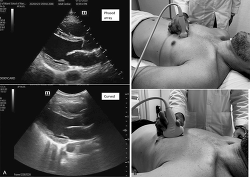

The clinician begins the RUSH protocol by evaluating the pump, or the heart. To evaluate the pump, a clinician can use three main different anatomical windows. The probe or transducer used for these views would be low frequency, 1-5 MHz, such as the phased array. The first one is the parasternal long view (Perera et al., 2010; Wacker & Winters, 2014). Placing the low-frequency phased array transducer on the anatomical left sternal border fourth intercostal space, the indicator will point toward the patient's anatomical left, specifically the left elbow diagonally if the ultrasound machine is in general mode. If the ultrasound machine setting is in cardiac mode, then the indicator should point diagonally toward the right shoulder (Perera et al., 2010; Wacker & Winters, 2014; see Figures 6 and 7).

Figure 6 - Click to enlarge in new windowFigure 6. (A) Parasternal long axis of the heart phased array and curved probe. (B) Curved and phased array probe position for parasternal long axis. Photograph courtesy of Juan M. Gonzalez.

Figure 7 - Click to enlarge in new windowFigure 7. (A) Probe position for cardiac mode. (B) Probe position for general mode. Illustration courtesy of Yusmel Jimenez. Reprinted with permission.

The second view of the heart can be obtained by placing the low-frequency phased array probe in the apical "four-chamber" view. The probe is placed in the transverse view, with the indicator to the patient's anatomical right toward the right iliac crest, just medially to the midclavicular line or left nipple, fifth intercostal space (Perera et al., 2010; Wacker & Winters, 2014; see Figure 8).

Figure 8 - Click to enlarge in new windowFigure 8. (A) Four-chamber view of the heart with phased array and with curved probe. (B) Probe position for four-chamber (apical) view of the heart with phased array and curved probe. LA = left atrium; LV = left ventricle; RA = right atrium; RV = right ventricle. Photograph courtesy of Juan M. Gonzalez.

The last view is the subxiphoid view, in which the probe is placed in the transverse plane, with the indicator pointing toward the patient's anatomical right, using the liver as an acoustic window (Gonzalez et al., 2019; Wacker & Winters, 2014). The probe is then tilted slightly to the left or subxiphoid area to visualize the heart (Gonzalez et al., 2019; Perera et al., 2010; Wongwaisayawan et al., 2015; see Figure 9).

Figure 9 - Click to enlarge in new windowFigure 9. (A) Subxiphoid view of the heart. (B) Curved probe position of the probe for subxiphoid view of the heart. Photograph courtesy of Juan M. Gonzalez.